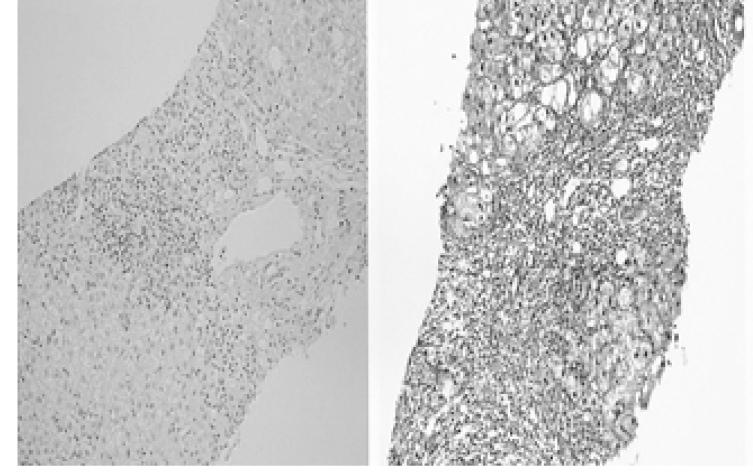

Aminotransferase levels do not always increase during acute hepatitis or during an acute flare-up of chronic hepatitis. Persistently increased levels of serum alpha-Fetoprotein in an adult with liver disease suggest not only the presence or progression of hepatocellular Carcinoma or its recurrence after hepatic resection or after other therapeutic approaches such as chemotherapy or chemoembolization, but also it suggests that there is an acute exacerbation of hepatitis or liver cirrhosis. We report here on two unusual cases of HBV- & HCV-related liver cirrhosis with acute exacerbation of hepatitis in which there was an insignificant elevation of the aminotransferase levels, but there were markedly increased alpha-Fetoprotein levels observed. The levels of alpha-Fetoprotein decreased gradually in both cases since the beginning of antiviral therapy, which implies that the increased levels were due to aggravation of the accompanying hepatitis. These cases also emphasize that using only the measurement of alpha-Fetoprotein is not sufficient for the diagnosis of hepatocellular carcinoma, and that this diagnosis also requires a more specific measurement such as AFP L3 along with the standard imaging studies.

在急性肝炎或慢性肝炎急性发作期间,转氨酶水平并非总是升高。患有肝病的成年人血清甲胎蛋白水平持续升高,不仅提示存在肝细胞癌或其进展,或肝切除术后或化疗、化疗栓塞等其他治疗方法后复发,还提示肝炎或肝硬化急性加重。我们在此报告两例不寻常的乙型肝炎病毒和丙型肝炎病毒相关肝硬化伴肝炎急性加重的病例,其中转氨酶水平仅有轻微升高,但甲胎蛋白水平显著升高。自抗病毒治疗开始后,两例患者的甲胎蛋白水平均逐渐下降,这意味着升高的水平是由于伴随肝炎的加重所致。这些病例还强调,仅通过甲胎蛋白检测不足以诊断肝细胞癌,该诊断还需要更具特异性的检测,如甲胎蛋白异质体L3以及标准影像学检查。